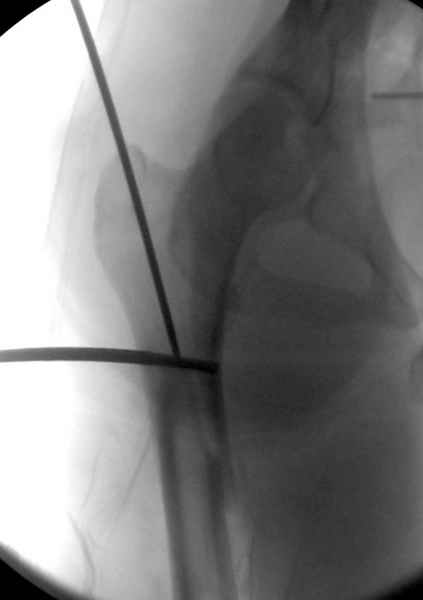

Второй случай тоже репозиция из малого доступа, больному 19 лет, множественные огнестрельные повреждениия конечностей, живота и черепа, правая конечность холодная, без пульсации. Ортопедический диагноз: огнестрельный перелом правого бедра. При срочной ангиографии повреждения сосудов не подтвердилось, конечность из-за ургентности состояния больного зафиксирована временным наружным фиксатором и больной оставлен на операционном столе для срочной лапаротомии хирургической службой.

Больной долго оставался нестабильным, только на 14 день удалось заменить на антеградный интромедуллярный штифт TFN (trochanteric femoral nail) SmithNephew. После неудачной попытки закрытой репозиции, несмотря на использование "joystick", проксимальный стержень от

наружного фиксатора, (перелом начал срастаться) репозицию провели из малого доступа, затем остальные этапы операции.